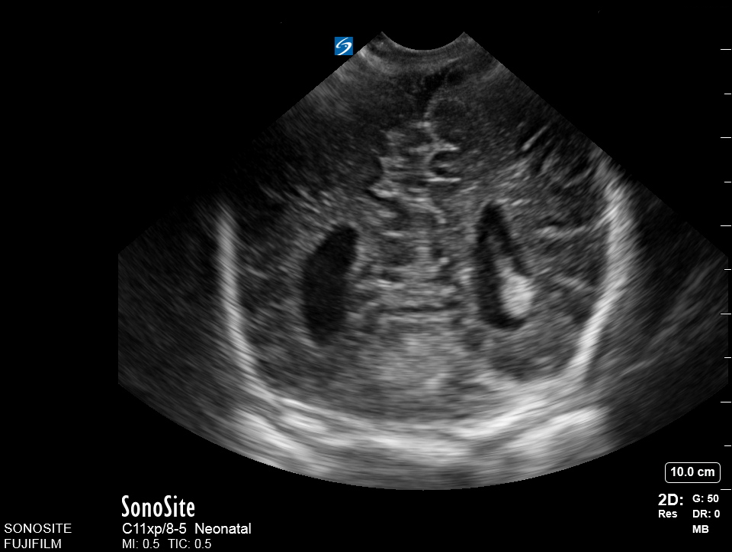

Neonatology Corpus Callosum Agenesis 4 Image